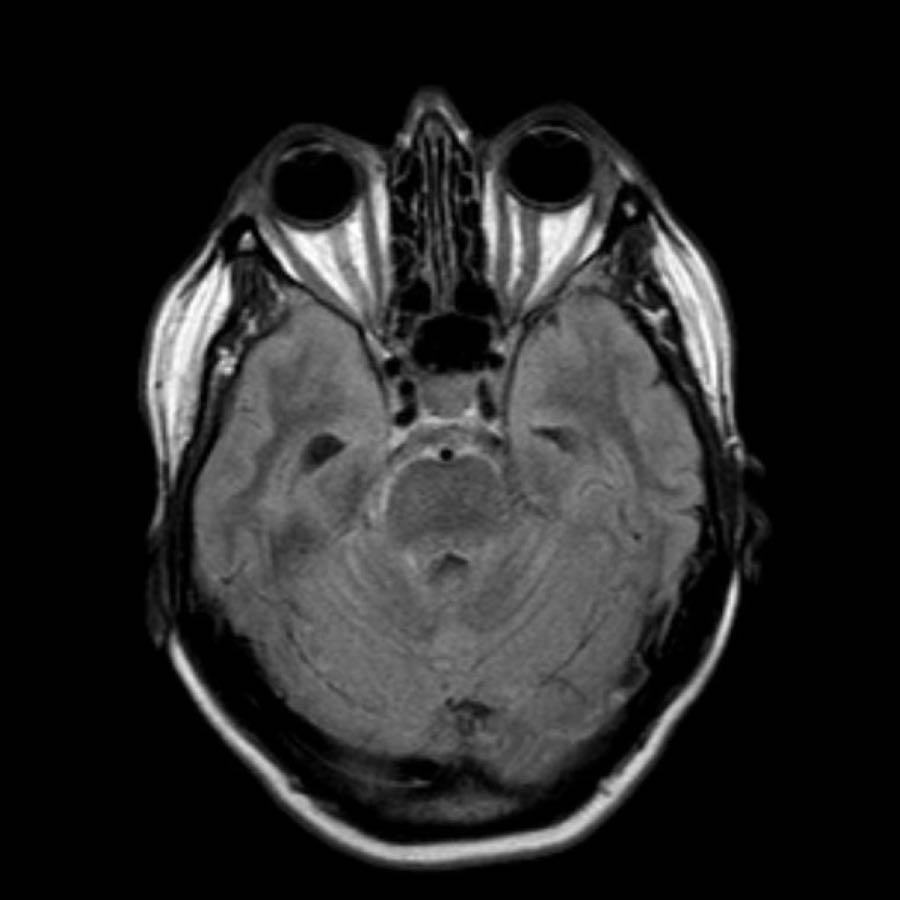

Bệnh nhân này nhập viện với xuất huyết tiểu não.

Các hình ảnh chuỗi xung gradient echo cho thấy nhiều vi xuất huyết.

Đây có thể là hậu quả của tăng huyết áp lâu năm do vị trí trung tâm của một số vi xuất huyết.